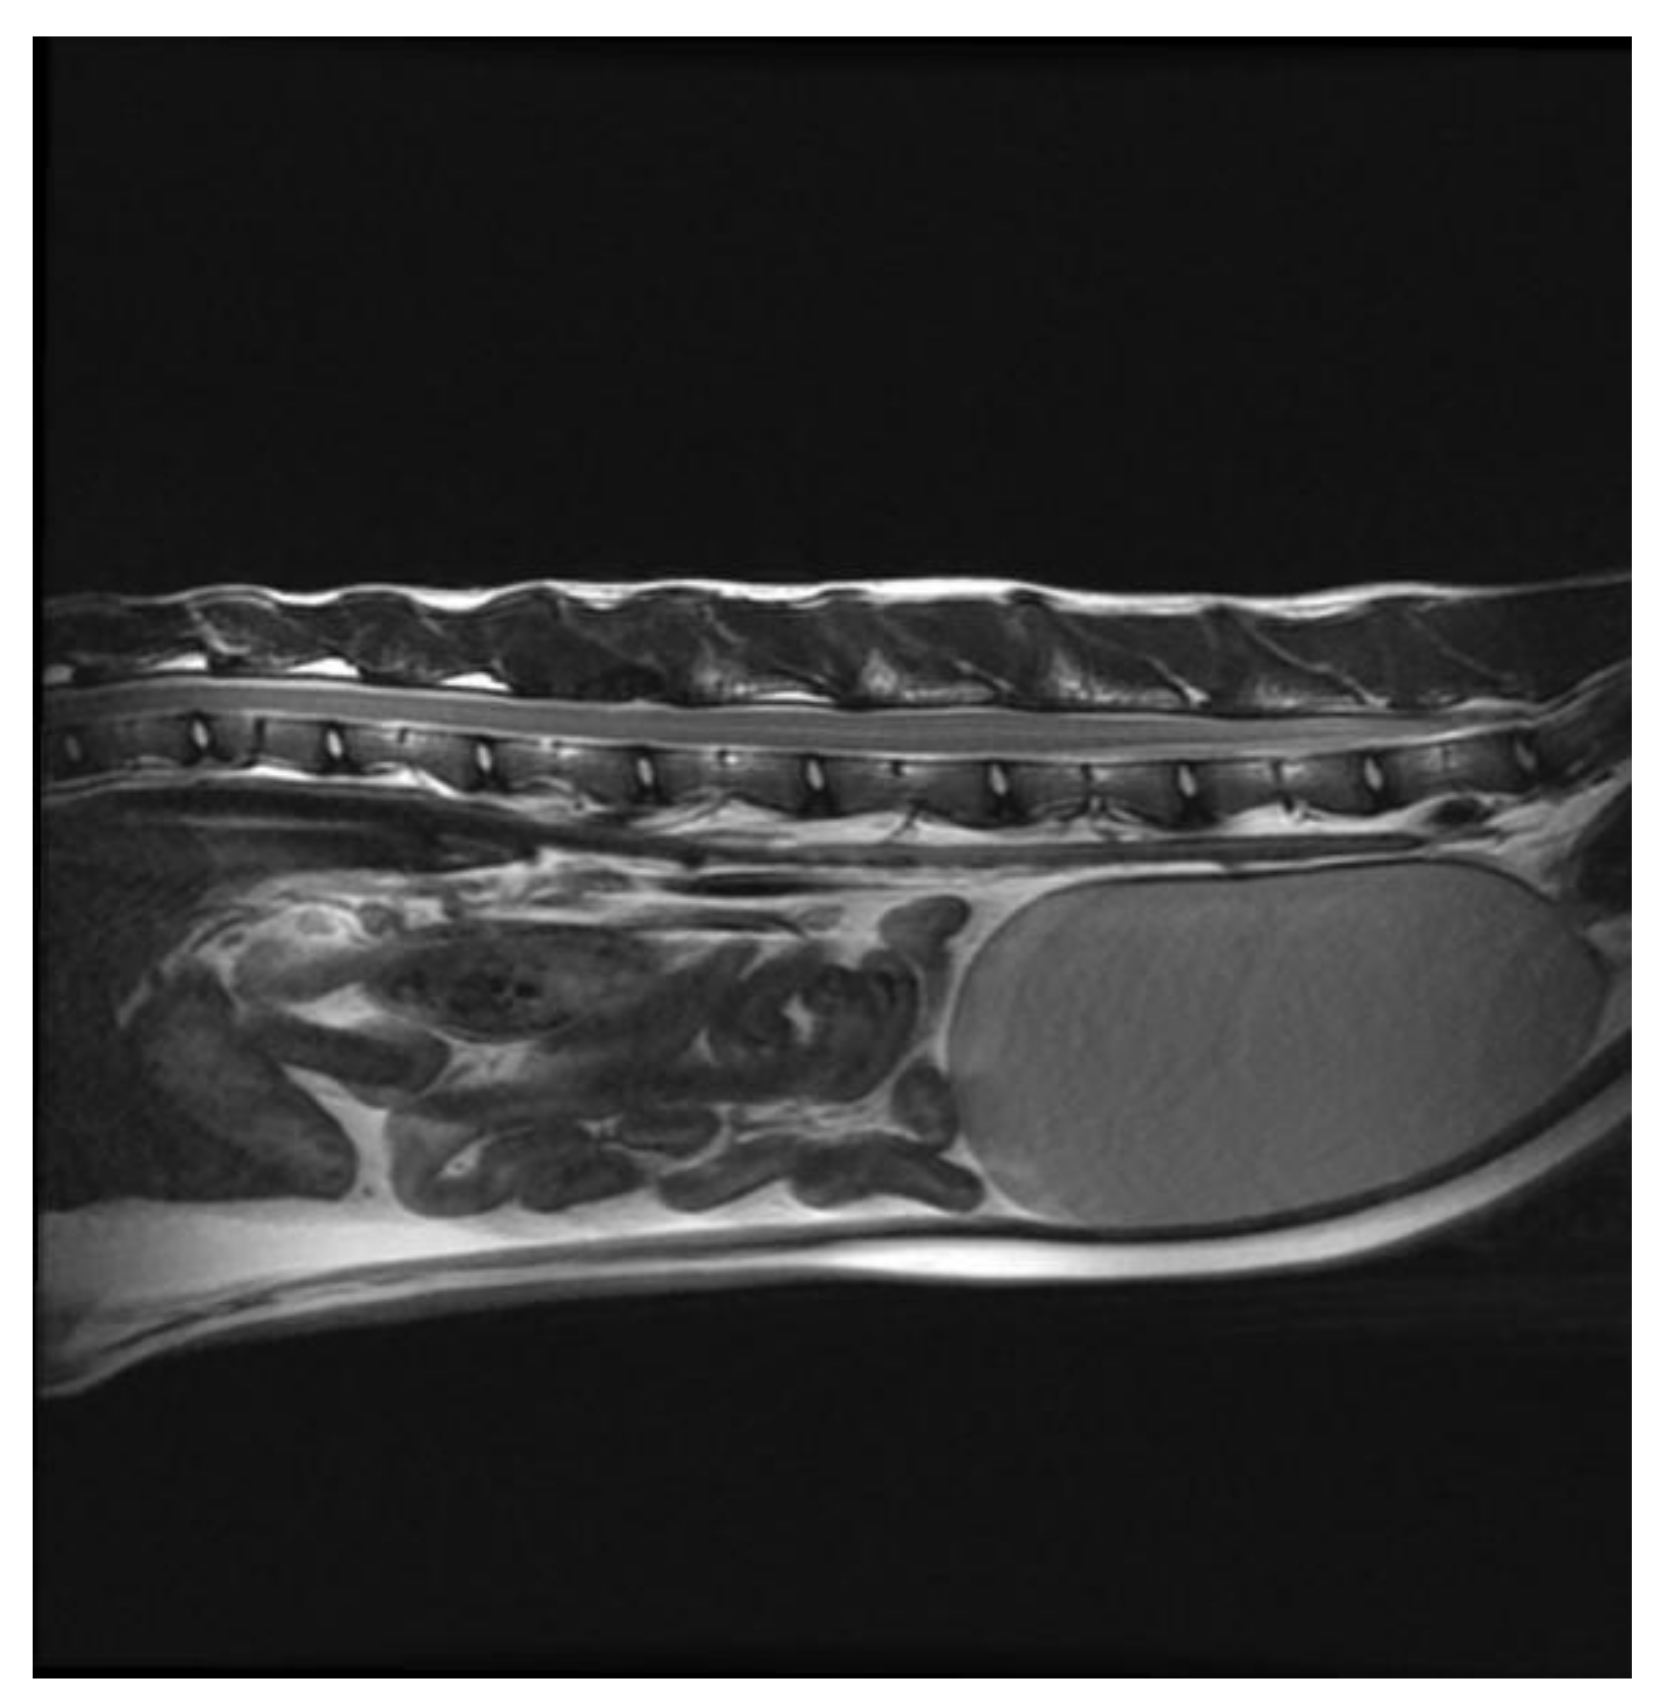

Successful Treatment of Vertebral Osteosarcoma in a Cat Using Marginal Surgical Excision and Chemotherapy

:1. Case Description